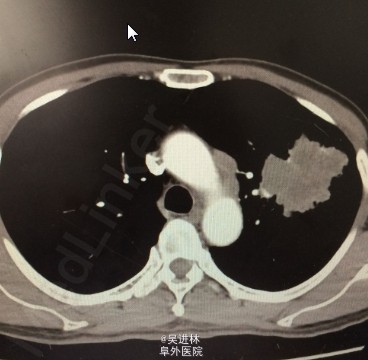

CT:左肺巨大肺癌

诊断:左肺鳞癌 处理:左全肺切除

讨论:这个病人预后很不好的,已经侵犯心脏了(探查肿物位于左肺上叶,直径约8厘米,质地硬,侵及肺门,左肺不张。打开肺门,胸膜水肿游离易渗血,检查肿瘤侵犯下肺静脉根部,无法游离。打开心包,探查肿瘤已沿下肺静脉进入心包,累及右心房。)